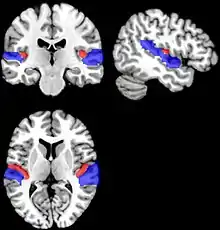

As brain regions particularly crucial in speech production are disconnected, it may cause persistent dysfluency. If the dysfluency continues into adulthood, researchers have found the basal ganglia and the attrition of white matter below the sensorimotor cortex in the brain as contributing factors.[15] In addition, because connections between the motor cortex and the basal ganglia are essential for speech production, dysfunctions in this area could be a cause of persistent developmental stuttering (PDS). PDS is the persistence of stuttering and other dysfluencies into adulthood. Researchers have proposed therapies to assist in speech production improvement, such as fluency shaping therapy.[15]

Adulthood stuttering is diagnosed as Persistent Developmental Stuttering (PDE). PDE patients can also express more external movements such as tic-like involuntary movements that non-PDE patients would not exhibit.[15] PDE patients vary in when their stuttering symptoms began, ranging from early childhood (ages 3-4) to later childhood. To treat PDE, patients can undergo fluency shaping therapy that has proven effective.[15]